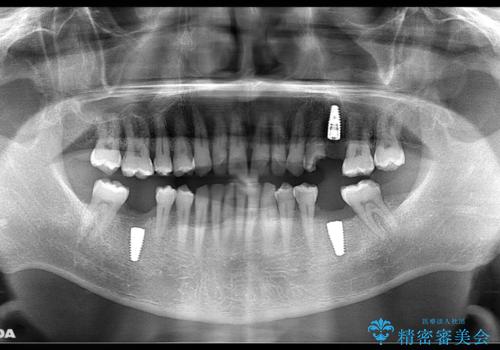

- リタイアを期に海外に移住されることになり、出発前に全顎的に治療をしておきたいと来院された患者様です。最短期間で治療を終了できるよう、事前に綿密な計画を立てたうえで集中的に治療を行いました。

期日が決まっていたため、それぞれの処置にかかる日数・時間を綿密に計算したうえで短期間での集中治療を行いました。毎回の処置時間を長めに設定し、1回の来院でより多くの処置を行えるようにしたおかげで全顎的な治療も短期間で仕上げることができました。